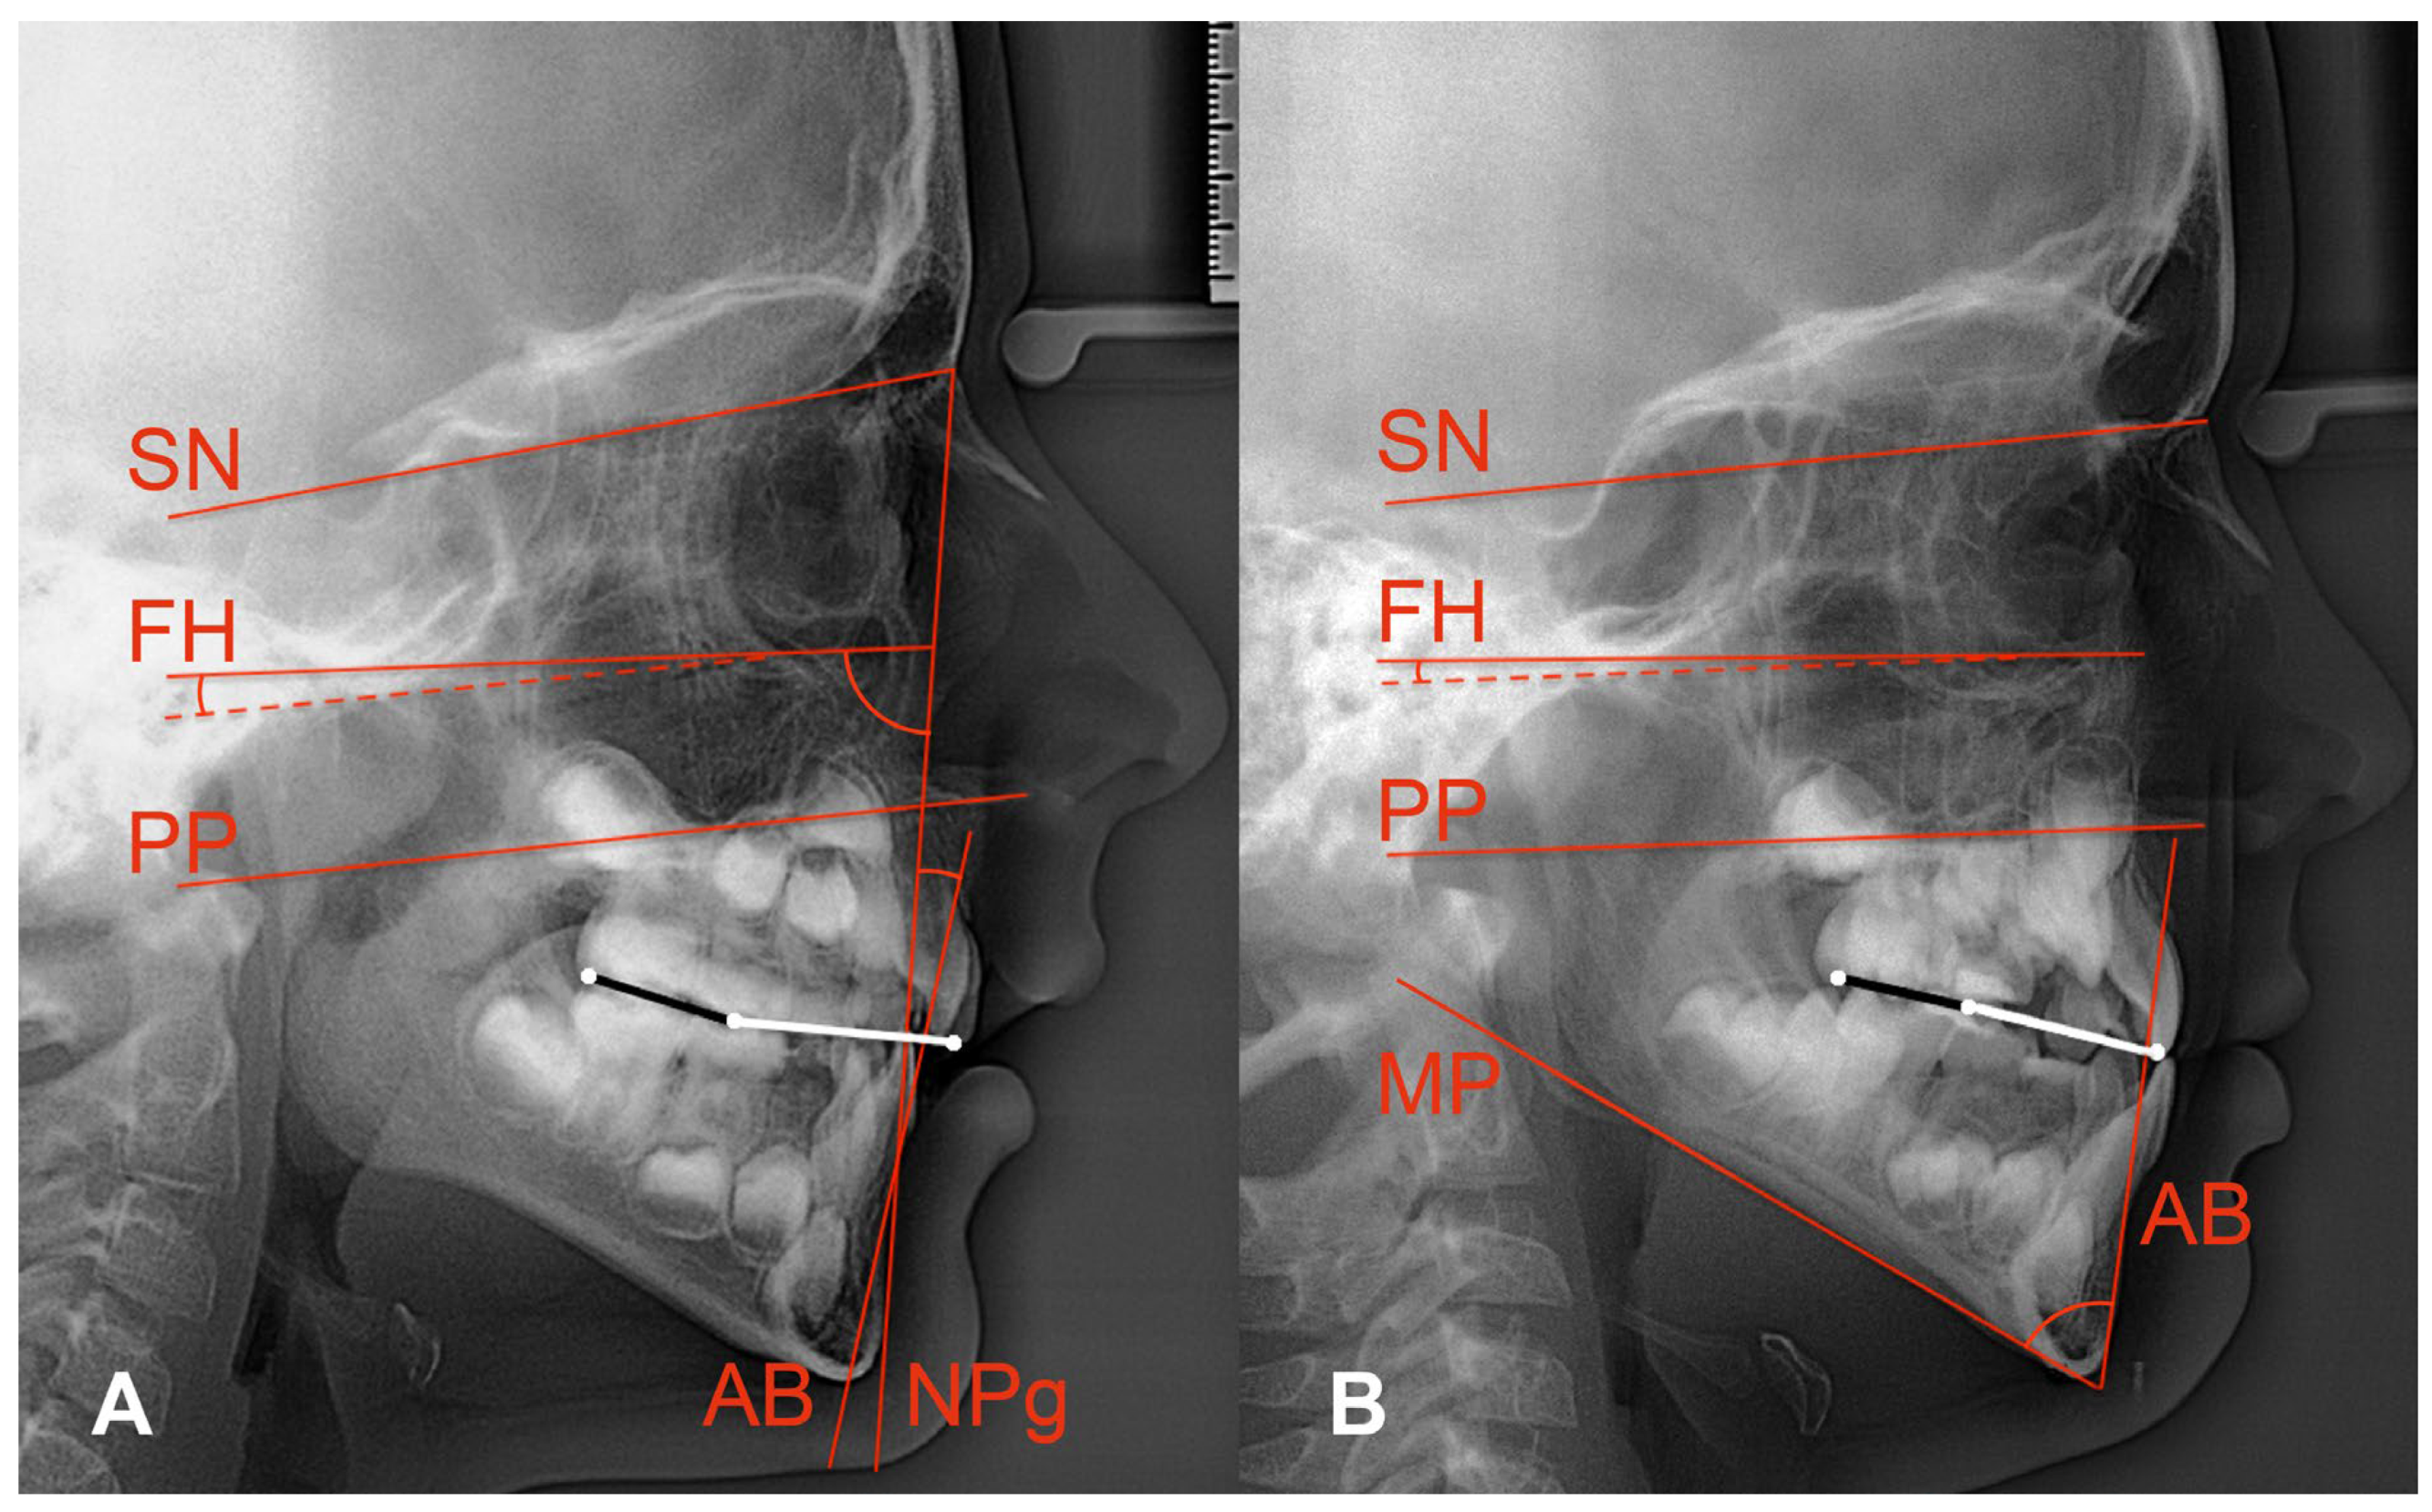

Diagnostic criteria comprised skeletal class II or skeletal class III as obtained from cephalometric radiographs. Same as Tanaka and Sato [6], we sampled our study groups according to the anteroposterior dysplasia indicator (APDI) [13]: class II when APDI < 77.5, class III when APDI > 85 (Figure 1A).

We located SN from the centre of the pituitary fossa to nasion, FH from averaged orbitale to averaged porion, palatal plane (PP) from anterior nasal spine to posterior nasal spine, mandibular plane (MP) from menton to averaged tangential gonion, the nasion-pogonion line (NPg), the line from point A to point B (AB), the maxillary incisor, and the averaged molar outlines (Figure 1).

As the original definitions of AOP and POP referred to permanent maxillary incisors, second premolars, and permanent second molars [4], we had to modify the delineations of AOP and POP for mixed dentitions: AOP connected the incisal edge of the maxillary central incisor and the midpoint between the cusp tips of the averaged maxillary deciduous second molars. The latter point and the distal cusp tip of the averaged permanent maxillary first molar defined the mixed dentition POP (Figure 1).

The cephalometric measurements included APDI, Wits appraisal, angles FH–AOP, FH–POP, SN–AOP, SN–POP, and the overbite depth indicator (ODI), a descriptor of vertical skeletal relationships [14]. The ODI adds the angle between FH and PP plus the angle between AB and MP. Angle FH–PP is read positive if PP slopes more forward–downward than FH. Figure 1B shows backward–downward inclined PPs, i.e., negative FH–PP angles. The ODI’s reference range is 74.5 ± 6.1 [14]. Six- to ten-year-old children from the Burlington growth study showed ODI means from 69.3 to 74.3. The greater the ODI, the more skeletal hypodivergence exists, and vice versa.

Figure 1. Anterior occlusal plane (white line) and posterior occlusal plane (black line) depicted for mixed dentitions of 2 non-participants showing skeletal class II (A) and skeletal class III (B) relationships. White occlusal dots show AOP and POP landmarks (maxillary incisor’s edge, occlusal midpoint of maxillary second deciduous molar, distal cusp of averaged permanent first molar). Red lines show SN and FH. (A) also illustrates the APDI: sum of the angles between Frankfort horizontal (FH) and nasion-pogonion line (NPg) plus/minus angle between FH and palatal plane (PP; negative signs in both examples) plus/minus angle between NPg and A–B line (AB; negative sign in (A)). (B) shows the ODI: sum of the angle between AB and the mandibular plane (MP) plus/minus angle between FH and PP.